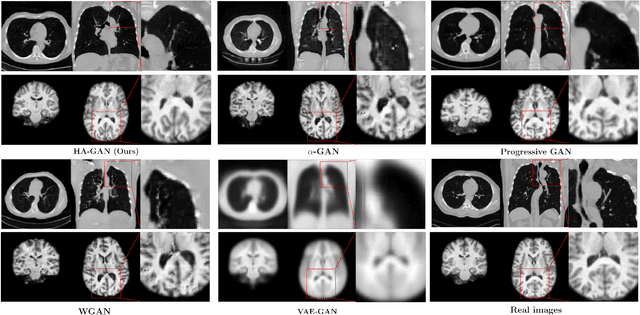

Generative Adversarial Networks (GAN) have many potential medical imaging applications, including data augmentation, domain adaptation, and model explanation. Due to the limited embedded memory of Graphical Processing Units (GPUs), most current 3D GAN models are trained on low-resolution medical images. In this work, we propose a novel end-to-end GAN architecture that can generate high-resolution 3D images. We achieve this goal by separating training and inference. During training, we adopt a hierarchical structure that simultaneously generates a low-resolution version of the image and a randomly selected sub-volume of the high-resolution image. The hierarchical design has two advantages: First, the memory demand for training on high-resolution images is amortized among subvolumes. Furthermore, anchoring the high-resolution subvolumes to a single low-resolution image ensures anatomical consistency between subvolumes. During inference, our model can directly generate full high-resolution images. We also incorporate an encoder with a similar hierarchical structure into the model to extract features from the images. Experiments on 3D thorax CT and brain MRI demonstrate that our approach outperforms state of the art in image generation, image reconstruction, and clinical-relevant variables prediction.